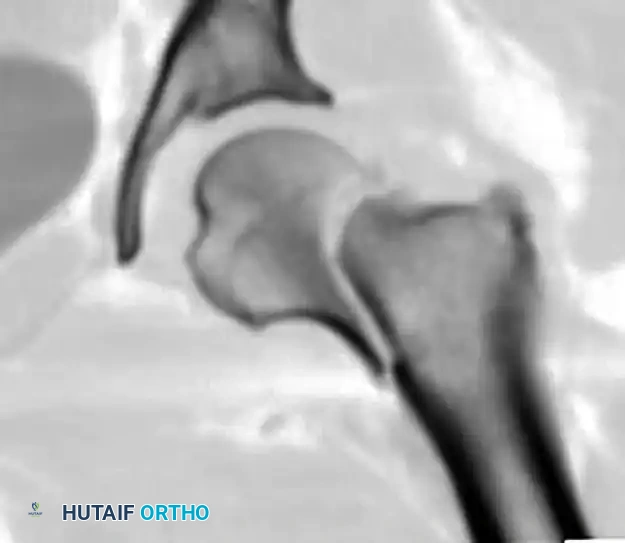

1. Internal Fixation (Joint Preservation)

Younger patients (typically < 60-65 years) with displaced or non-displaced fractures, and older patients with strictly non-displaced (Garden I/II) fractures, are treated with internal fixation. The goal is absolute stability to allow for revascularization and bony union.

Cannulated Screw Fixation:

The standard construct involves three 6.5mm or 7.0mm partially threaded cannulated screws placed in an inverted triangle configuration.

* The inferior screw is placed first, resting directly on the dense bone of the calcar femorale to resist varus collapse.

* The anterior and posterior screws are placed superiorly to resist rotational forces.

Sliding Hip Screws (SHS):

For basicervical fractures or vertical shear patterns (Pauwels Type III), a sliding hip screw with a derotational screw provides superior biomechanical stability against shear forces compared to multiple cannulated screws.

Surgical Progression for Internal Fixation:

The following diagrams illustrate the progression of guide wire placement, measurement, and final screw insertion to achieve stable osteosynthesis.

Initial guide wire placement targeting the inferior calcar and central femoral head.

Placement of the superior guide wires to form the inverted triangle configuration.

Measuring for screw length. Screws must be advanced to within 5mm of the subchondral bone to maximize purchase in the dense trabeculae.

Final seating of the partially threaded cannulated screws, allowing for dynamic compression across the fracture site.